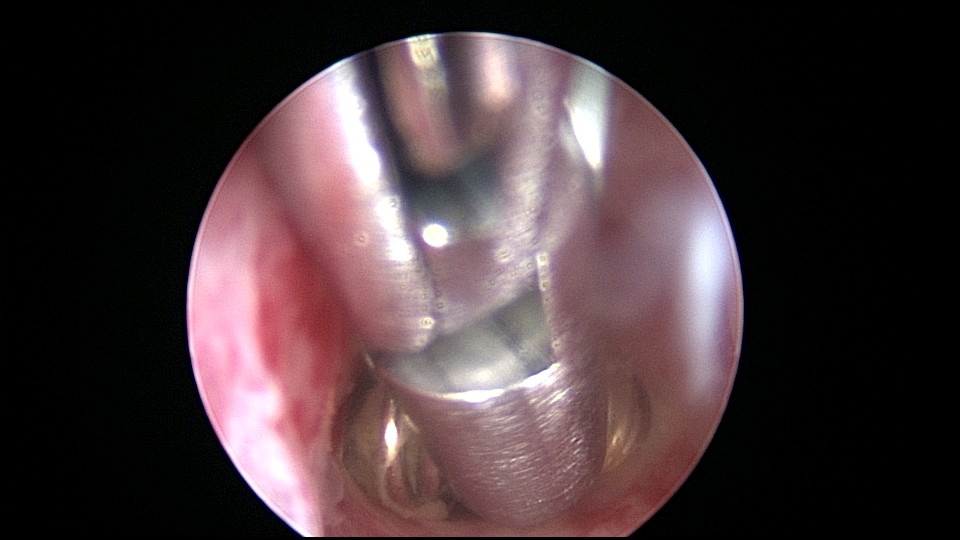

患者58岁,G2P1,顺产1次。安环35年,绝经15年,5年前在外院取环失败。术前B超提示子宫后位,O型环嵌顿,环顶端距宫底0.7cm。宫腔镜术中见阴道口狭小,无法置入窥阴器,宫颈外口狭窄,镜鞘缓慢扩大。宫颈内口粘连,左侧似有一小孔,异物钳扩大小孔,见较多浓稠黄色液体流出,冲洗干净后推进宫腔镜,见2个O型节育环,上面的环取出顺利,下面那个环与宫腔侧壁嵌顿,2次牵拉滑脱,第三次一张一驰松动节育环,再缓慢拉出,宫底见2道环压痕。